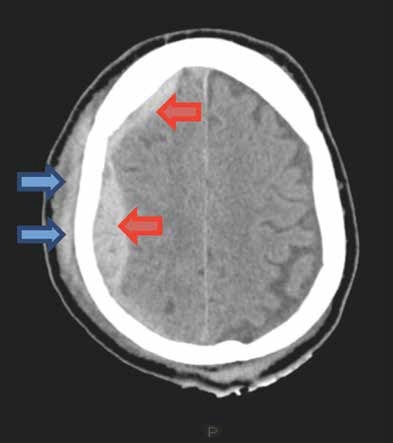

A: Vias aéreas pérvias, com colar cervical. B: Murmúrios vesiculares presentes bilateralmente; expansibilidade simétrica; tórax indolor à palpação; sem crepitações; FR = 16 irpm; saturação de O2 98% em ar ambiente. C: Pulso = 108 bpm; pressão arterial = 120 x 70 mmHg; sem sangramento visível. Abdome doloroso à palpação em epigástrio e mesogástrio, onde se evidenciam equimose e escoriação. Toque retal sem alterações, diurese clara. D: Escala de Coma de Glasgow = 15; pupilas isocóricas e fotorreagentes. E: Sem outras alterações. Realizada expansão volêmica com 2.000 ml de soro fisiológico e analgesia. Após essas medidas, o paciente apresenta frequência cardíaca de 86 bpm e pressão arterial de 120 x 70 mmHg. Devido ao traumatismo craniano, associado à cefaleia atual, foi solicitada

tomografia computadorizada de crânio com a imagem apresentada.

Cite a conclusão do laudo desta imagem:

A imagem apresentada no enunciado é de uma Tomografia Computadorizada (TC) de crânio, e disso ninguém duvida. Nesse momento devemos nos fazer uma pergunta óbvia: esse paciente tem indicação

de ser submetido a tal exame? Sim, tem. Embora

esse jovem tenha um Trauma Cranioencefálico (TCE)

leve (Escala de Coma de Glasgow entre 13-15), ele tem indicação de TC, pois apresenta cefaleia intensa. Vamos recordar as principais indicações de TC de crânio no TCE leve: cefaleia intensa, suspeita de fratura aberta de crânio, sinais de fratura de base de crânio, mais de dois episódios de vômito, indivíduos acima de 65 anos, perda da consciência por mais de 5 minutos, amnésia retrógrada por mais de 30 minutos e deficit neurológico focal atribuído ao cérebro.

Voltando a TC do enunciado (FIGURA 1), o que encontramos? Observem uma imagem hiperdensa (branca) entre os sulcos (setas amarelas), uma região

que deveria ser hipodensa (preta), pois é preenchida por liquor. Essa imagem hiperdensa representa sangramento difuso entre os sulcos. Não temos imagem hiperdensa biconvexa, para pensarmos em hematoma epidural, nem imagem hiperdensa que acompanha a convexidade cerebral, para considerarmos o diagnóstico de hematoma subdural. Sendo assim, o nosso diagnóstico é de uma hemorragia subaracnóidea traumática. Alguns candidatos responderam hematoma intraparenquimatoso, mas vejam como a imagem de uma coleção parenquimatosa é bem diferente da apresentada no enunciado (FIGURA 2).